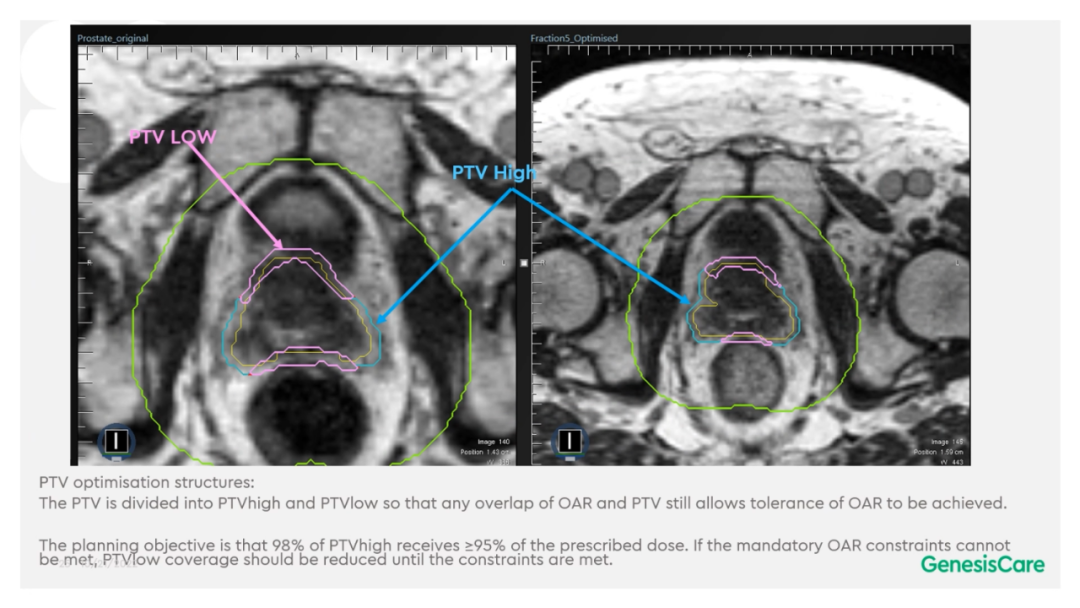

Dr. CamilleriÌåÏÖ£¬£¬£¬£¬£¬£¬ËûÃÇÔÚ×öÔÚÏß×Ô˳Ӧ·ÅÁƵÄʱ¼ä£¬£¬£¬£¬£¬£¬ÎªÁËÌá¸ßËÙÂÊ£¬£¬£¬£¬£¬£¬½ö¶Ô°ÐÇøÍâ·Å3cmÒÔÄÚµÄΣ¼°Æ÷¹ÙµÄת±ä¾ÙÐÐ×Ô˳Ӧµ÷½â»òÖØÐ¹´»ÂÖÀª£¬£¬£¬£¬£¬£¬¼ûFigure 13¡£¡£¡£¡£¡£¡£¡£ÕâÑù¿ÉÒÔËõ¶ÌÂÖÀª¹´»µÄʱ¼ä¡£¡£¡£¡£¡£¡£¡£¹ØÓÚ·ÅÁÆÍýÏ룬£¬£¬£¬£¬£¬Ê¹µÃ95%µÄ°ÐÇøÌå»ý½ÓÊܵ½100%µÄ´¦·½¼ÁÁ¿ÁýÕÖ£¬£¬£¬£¬£¬£¬²¢½«×î´ó¼ÁÁ¿ÏÞÖÆÎª2%µÄ°ÐÇøÌå»ý²»Áè¼Ý´¦·½¼ÁÁ¿µÄ110%£¬£¬£¬£¬£¬£¬ÕâÑù¾ÍÄܰü¹ÜÔÚͼÏñÉϺÜÄÑÏÔʾµÄÄòµÀ²»»á³¬Á¿£¬£¬£¬£¬£¬£¬¼ûFigure 14¡£¡£¡£¡£¡£¡£¡£ÁíÍ⣬£¬£¬£¬£¬£¬ÔÚÖÆ×÷·ÅÁÆÍýÏëʱ£¬£¬£¬£¬£¬£¬½«PTV·ÖΪPTV LOWºÍPTV High£¬£¬£¬£¬£¬£¬PTVºÍΣ¼°Æ÷¹ÙÖØµþµÄ²¿·ÖΪPTV LOW£¬£¬£¬£¬£¬£¬½«PTV LOWµÄ¼ÁÁ¿Ä¿µÄÉ趨ÔÚΣ¼°Æ÷¹ÙµÄÄÍÊܼÁÁ¿ÒÔÏ£¬£¬£¬£¬£¬£¬ÕâÑù¾ÍÄܰü¹ÜΣ¼°Æ÷¹Ù²»³¬Á¿£¬£¬£¬£¬£¬£¬¼ûFigure 15¡£¡£¡£¡£¡£¡£¡£